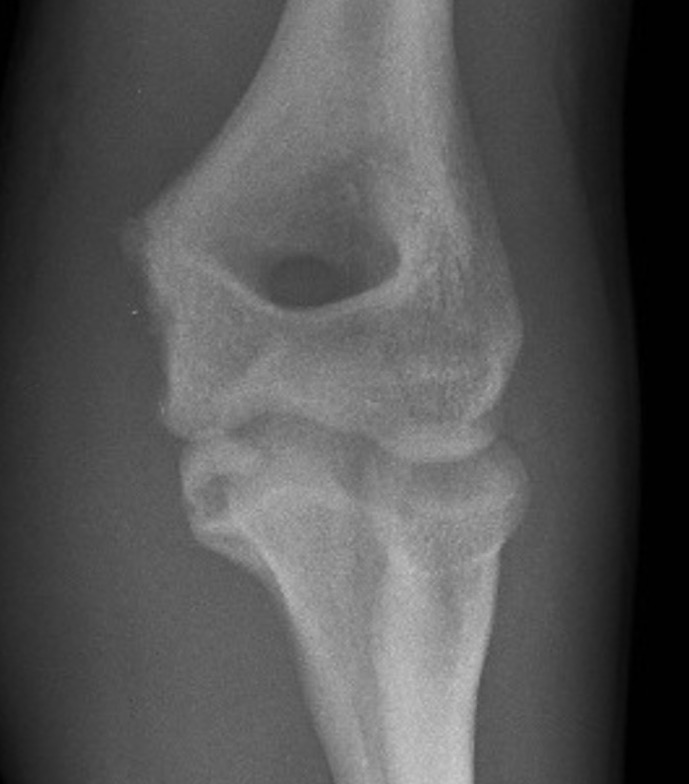

Xray

Displaced medial epicondyle fracture

Incarcerated medial epicondyle fracture